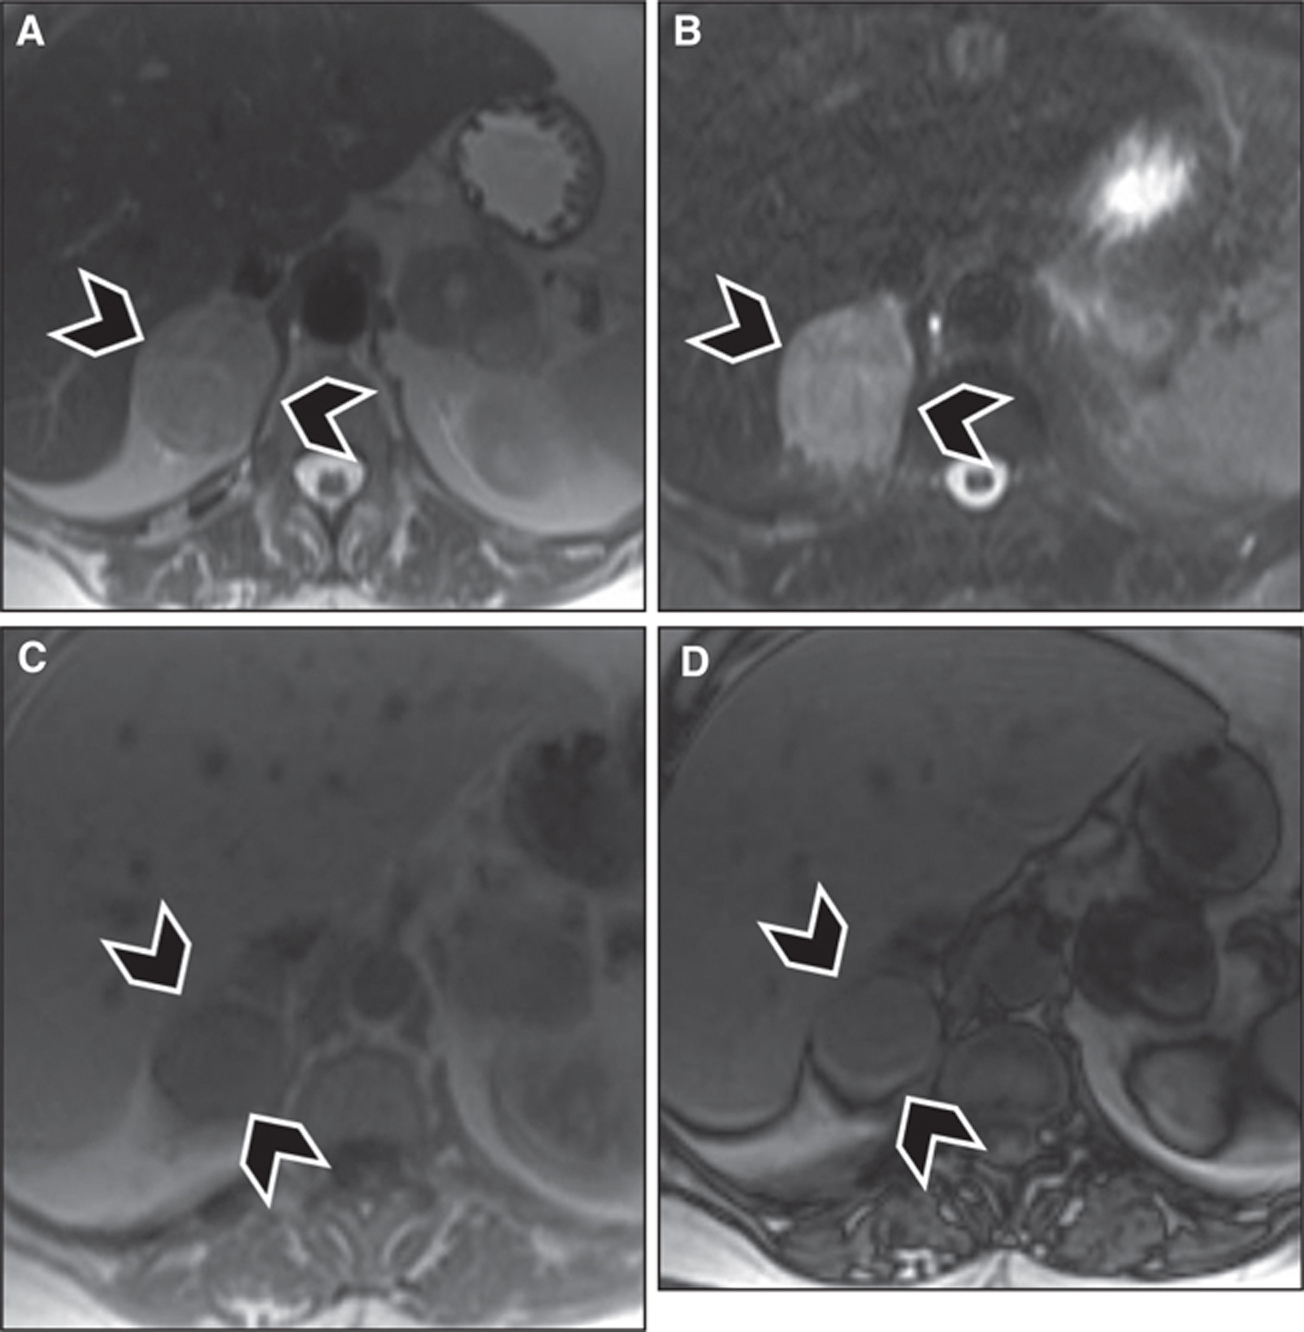

Magnetic resonance imaging

On MRI, like most tumors, pheochromocytomas demonstrate hypointense signal on T1 weighted images and hyperintense signal on T2 weighted images. This rather noncharacteristic appearance renders MR nonspecific for the diagnosis of pheochromocytoma, despite its high sensitivity. Classically, pheochromocytomas were described to have a very hyperintense signal on T2 weighted images, giving them a “light bulb” manifestation; this sign is distinctive in only 10% of lesions but might be helpful in two-thirdsd of pheochromocytomas (23). Another classical sign of paragangliomas, seen both on T1 and on T2 weighted images, is “salt-and-pepper” appearance, which is seen due to the presence of punctate areas of low-signal intensity corresponding to flow voids from tumor vascularity, and hyperintense signal corresponding to areas of hemorrhage in the tumor. This sign has been described more with head and neck paragnagliomas than with trunk paragnagliomas, and is also neither sensitive nor specific, as it can be seen with any hypervascular tumor, namely, in angiofibromas (19). Chemical shift imaging can diagnose intralesional microscopic fat such as that typically seen in adrenal adenomas, but it does not accurately differentiate adenomas from pheochromocytomas because the latter can contain intralesional fat from lipid degeneration (24, 25). Signal heterogeneity within the tumor due to hemorrhage, cystic transformation, and calcifications remains a helpful feature in differentiating pheochromocytomas from benign adenomas (Figure 5). Paragangliomas again demonstrate imaging features similar to pheochromocytomas. Enhancement characteristics on MRI are similar to CT, as PPGLs demonstrate rapid and avid enhancement, but up to one-third of pheochromocytomas have overlapping washout characteristics with adrenal adenomas (20, 21).

Fig 5

Figure 5 Right adrenal pheochromocytoma (arrowheads) in a 72-year-old female patient. Nonspecific signal intensity characteristics are seen, with intermediate to hyperintense signal seen on (A) T2-weighted images and (B) fat-suppressed T2-weighted images (turbo Inversion Recovery sequence), and hypointense signal seen on (C) in-phase T1-weighted images, and no signal loss on (D) out-of-phase images to suggest intralesional microscopic fat.